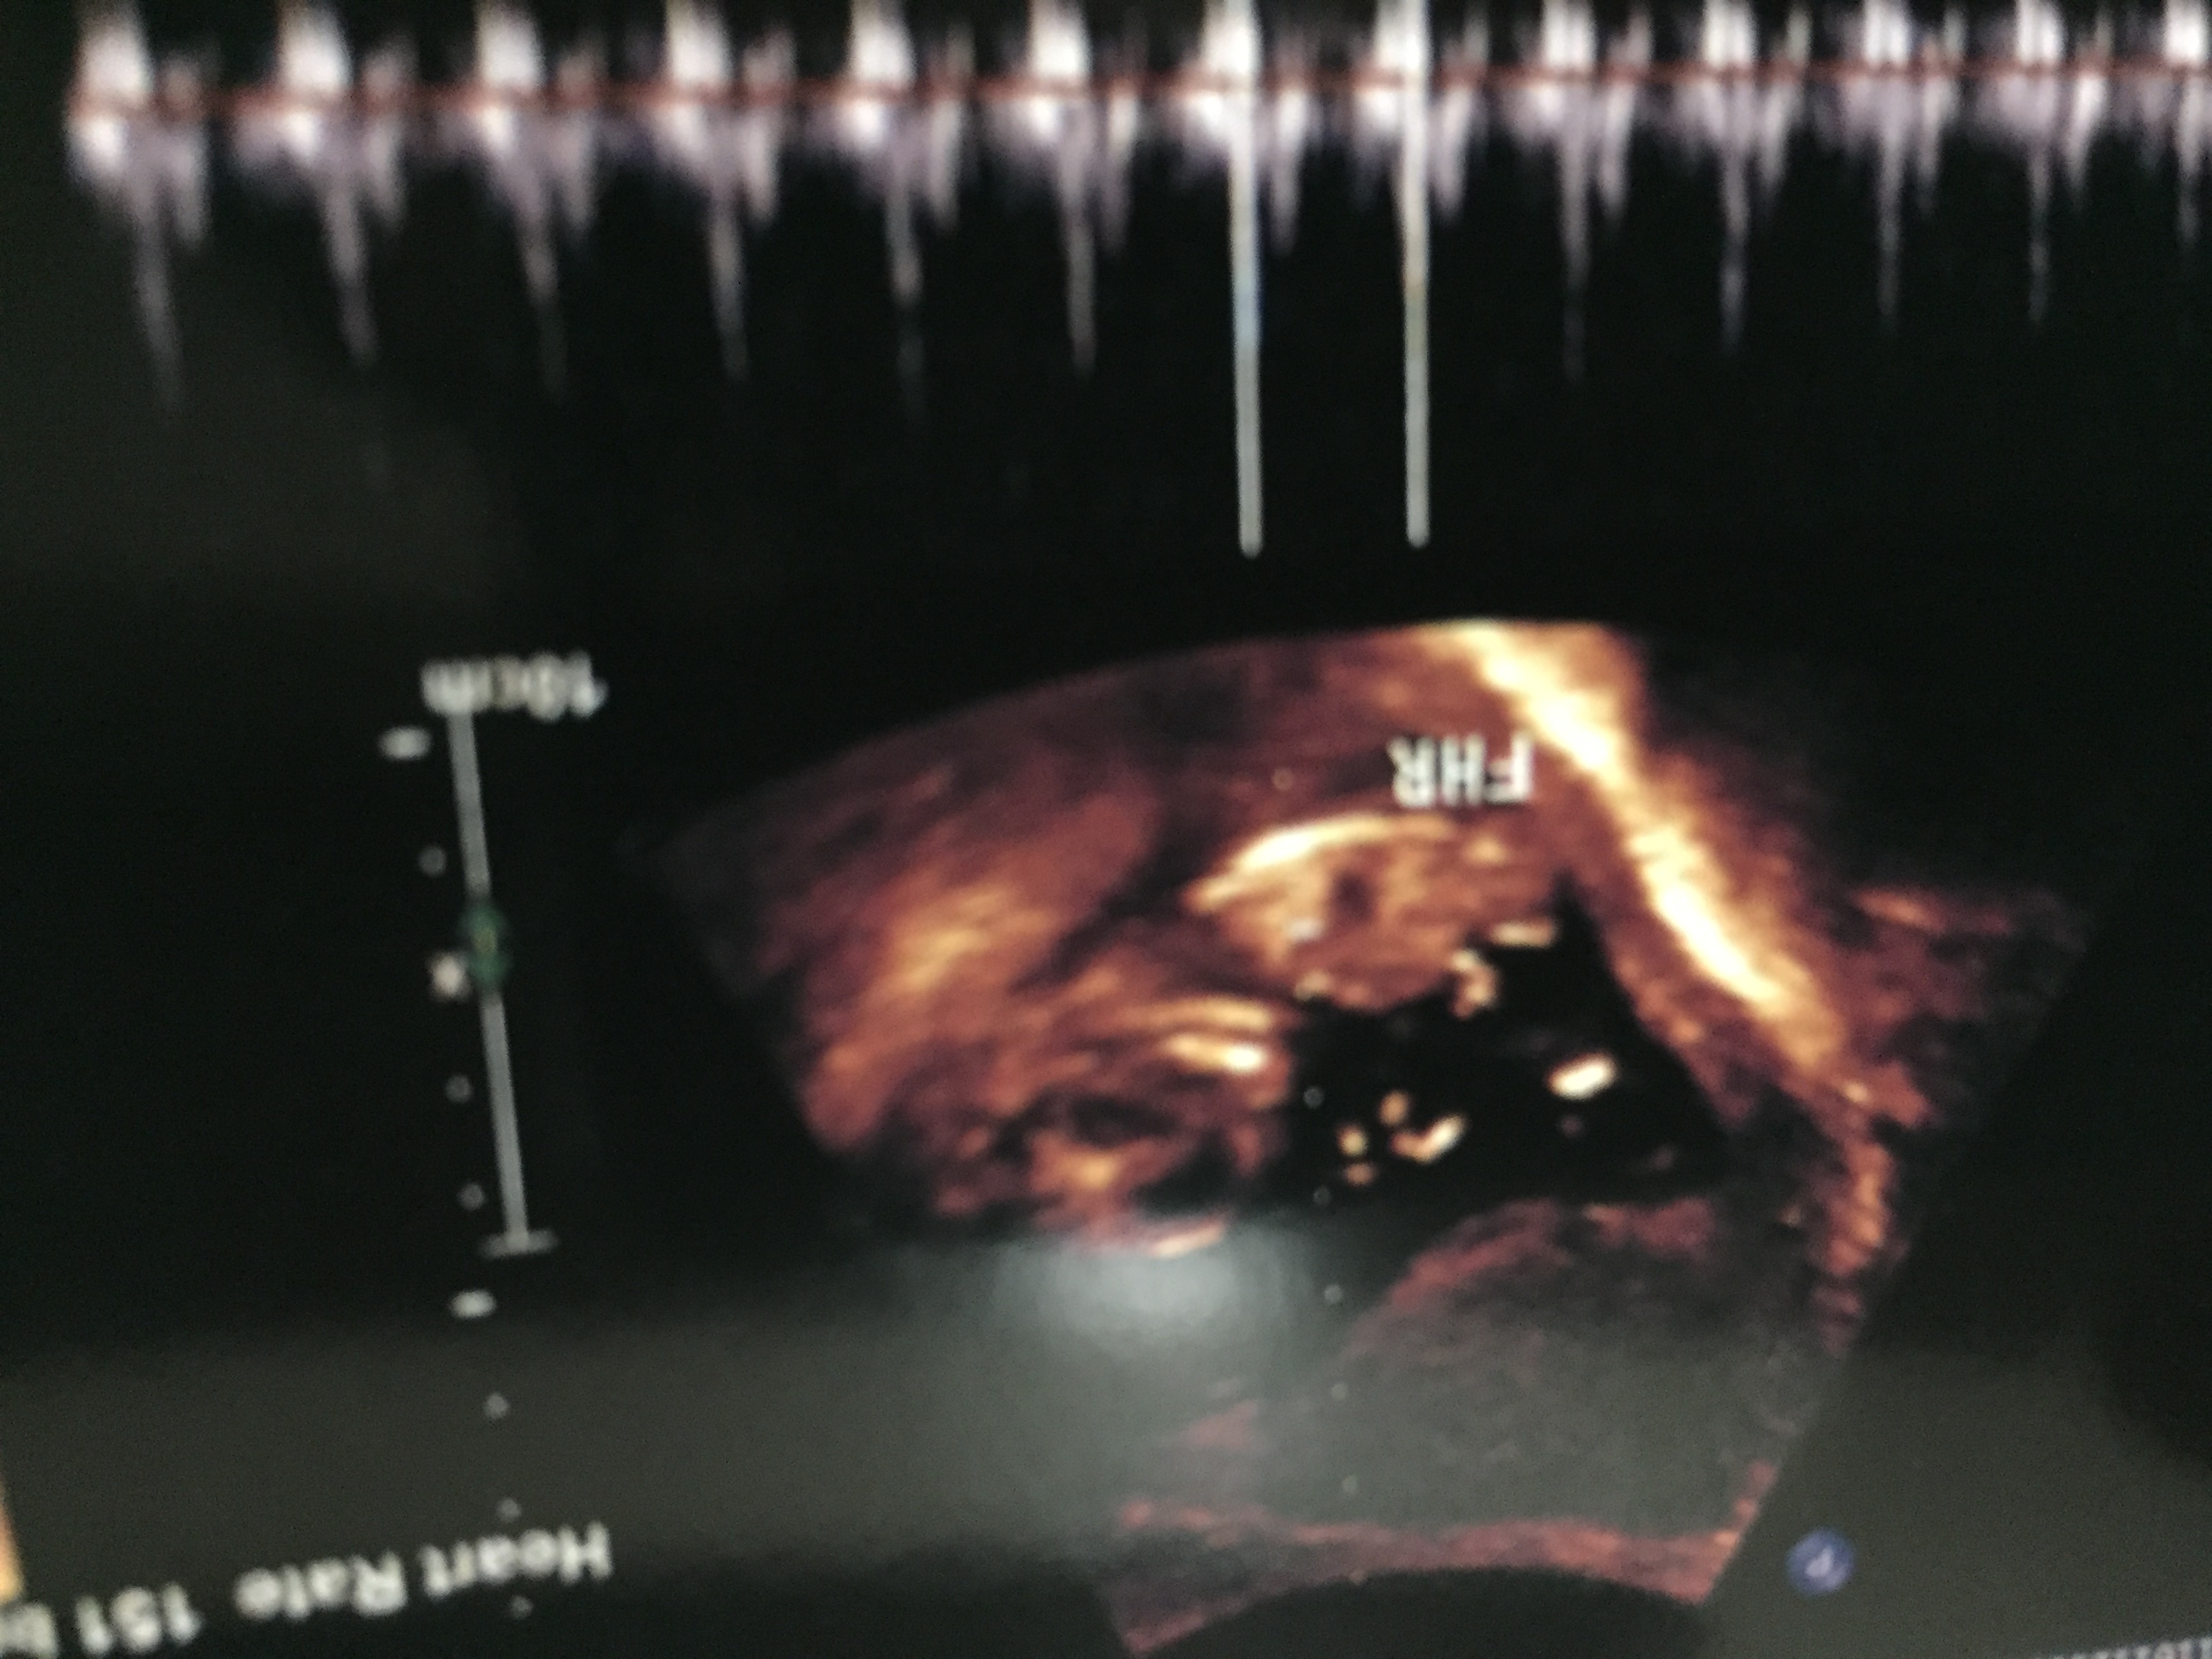

Attachment 39498Attachment 39499Attachment 39500Attachment 39501Attachment 39502

Guessing boy